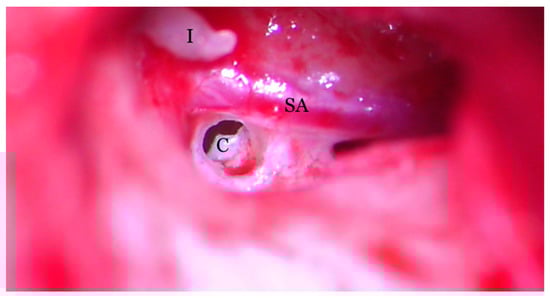

Hearing loss in patient’s right ear (with PSA) was addressed by performing an ossiculoplasty with a total ossicular replacement prosthesis (TORP). After a thorough preoperative planning based on prior surgical middle ear exploration and CT imaging, a transcanalar approach to the middle ear was used. A standard tympanomeatal flap was raised and the PSA was inspected. Large dimensions, complete coverage of the oval window site and crossing over the round window niche were again noted (Figure 7). The PSA went superiorly across the promontory and entered the facial nerve canal at the level where the normal oval window niche would have been located. Successful cochleostomy was carried out with a diamond burr posteriorly to the PSA and inferiorly to the facial nerve canal. Perichondrium was used to seal the cochlea opening and also served as a support for a total replacement ossicular prosthesis (Figure 8). The TORP was seated in place and covered with a mixed graft of cartilage and perichondrium with the tympanic membrane on top of it (Figure 9 and Figure 10).

Figure 8.

Transcanalar microscopic aspect of the right middle ear: the cochleostomy (C) orifice can be observed in the near vecinity of the stapedial artery (SA) and facial nerve (FN). The long process of the incus (I) can also be observed.